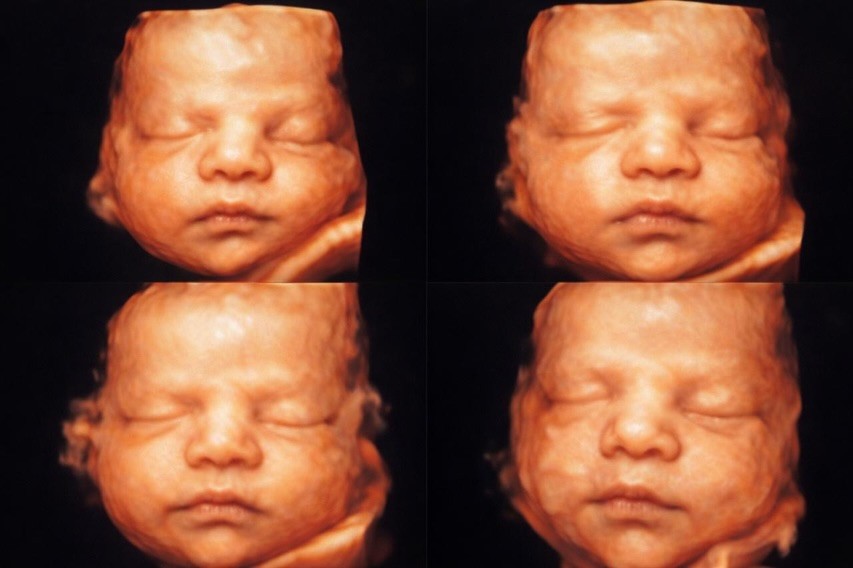

Patricia Leitte publica imagens do rosto de seu filho em ultrassom

Momento fofura! Durante a tarde desta sexta-feira (3), Patrícia Leitte compartilhou imagens do ultrassom de seu filho, Isaac Lucca. Em um relato emocionante, a ex-BBB descreveu como foi inesquecível conseguir ver o rostinho do bebê pela primeira vez.

"Nosso Isaac Lucca resolveu dar um presente pra gente: mostrou o rostinho no ultrassom… e que emoção foi ver aquele pedacinho do céu tomando forma diante dos nossos olhos", declara.

Patricia Leitte compartilha fotos do rosto de seu filho em ultrassom

Na postagem, a ex-participante do BBB 18 definiu o momento como inesquecível e destacou a intensidade da emoção à espera da chegada do filh

“Depois de tanta espera, orações e sonhos, ver você assim, meu filho, é como tocar uma promessa viva de Deus. Cada detalhe seu é prova de que Ele cumpre tudo o que promete", completa.